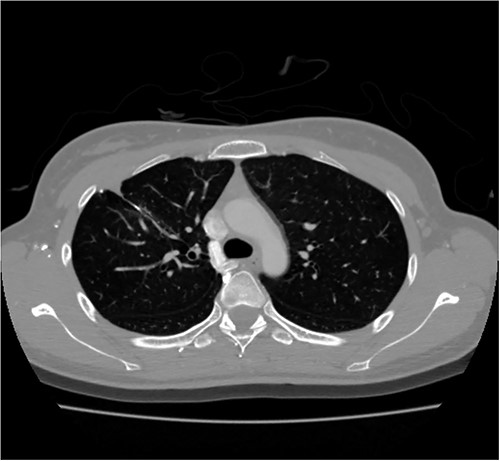

A 24-year-old female in the 21st week of pregnancy was transferred to the emergency department. Twelve hours before admission, the patient developed a tearing pain from the back to the right chest and dyspnea. There was no relevant medical history. Vital signs were systolic blood pressure of 83 mmHg, diastolic blood pressure of 58 mmHg, and pulse rate of 142/min. Initial hemoglobin level was 8.9 g/dl with a platelet count of 99 000/μl. Chest radiographs revealed a massive right pleural effusion with a mediastinal left shift (Fig. 1a). A closed thoracostomy was performed, and 2 l of blood was drained from the pleural cavity. Contrast-enhanced chest computed tomographic scan revealed a potentially ruptured PAVM in the anterior segment of the right upper lung (Fig. 1b). The patient was transfused with five packs of red blood cells and two packs of frozen fresh plasma. Emergency video-assisted thoracoscopic surgery (VATS) was performed. A 5-cm-sized working widow was created in the fifth intercostal space mid-axillary line. Two additional 10.5-mm ports were inserted in the sixth and seventh intercostal spaces in the anterior and posterior axillary lines. A half-liter of blood clots were removed. The PAVM, active bleeding on soft palpation, was visible on the right upper lung surface and was resected with two endostaples (Fig. 2). The patient developed disseminated intravascular coagulation and acute kidney injury postoperatively and was managed in the intensive care unit (ICU) for 3 days. She was recovered and was discharged 6 days after the operation without residual complications. The fetus had no particular problems related to the operation. However, it was miscarried after hydrocephalus and pericardial effusion were discovered. A follow-up computed tomographic scan 8 months after the operation revealed no residual PAVM (Fig. 3).

Contrast-enhanced chest CT after 8 months. Chest radiograph reveals no residual PAVM.